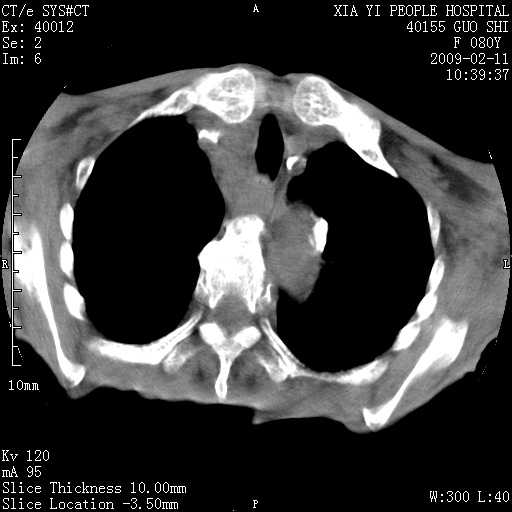

以下是引用随光逐影在2009-2-16 16:34:00的发言:[br]1)考虑右前纵隔皮样囊肿。2)双侧少量胸腔积液。

以下是引用zjzjr在2009-2-16 17:30:00的发言:[br]支持囊性畸胎瘤 双侧少量胸腔积液。